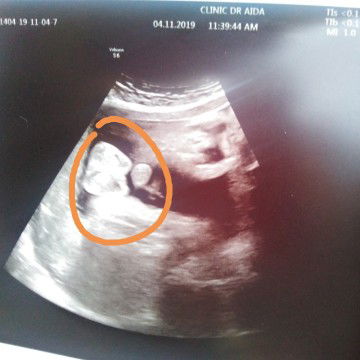

BOY KE?

Semalam check up Dr utk 36 week. Doktor kata Baby awak boy. Saya pun tanya dgn doktor tu balik. Betul ke boy doktor. Kata nya ye. Sbb nmpk soktrum ke apa die sebut. Saya pun krg jelas dgr sbb telinga saya rasa bengal sejak masuk air. ? Siapa pernah scan baby boy nmpk benda yg saya bulat kan tu?